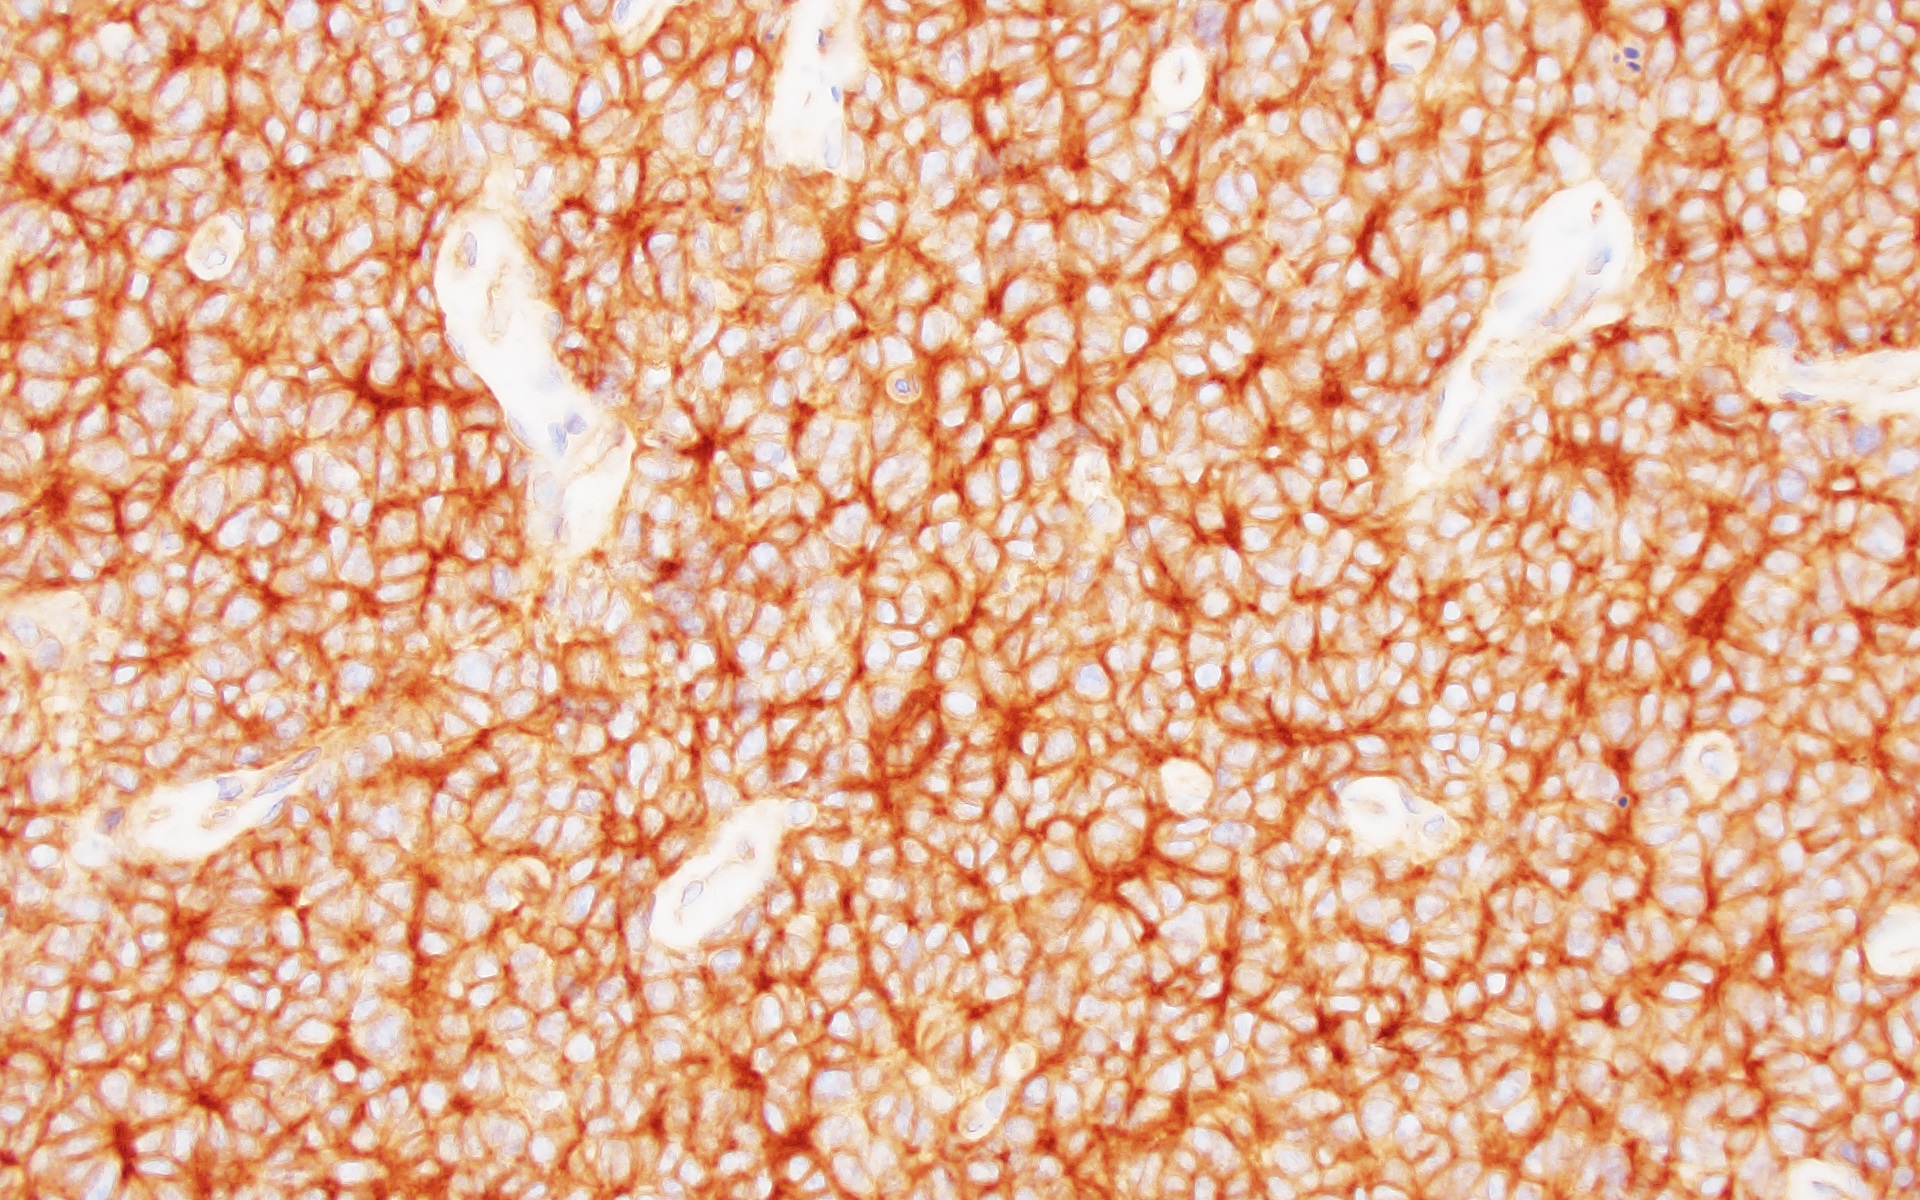

Representative Histology / IHC:

Histology from the resection reveals sheets of monomorphic tumor cells with high nuclear to cytoplasmic ratio, clumpy chromatin, frequent apoptotic bodies, and numerous mitotic figures. In other areas, the tumor shows necrosis and infiltration of the dura.

By immunohistochemistry, the tumor cells are diffusely positive for CD99 (membranous) and Nkx2.2 (nuclear). Tumor cells show retained nuclear expression of INI1, BRG1, and H3K27me3. The tumor cells are negative for GFAP, Olig2, synaptophysin, BCOR, desmin, and myogenin.